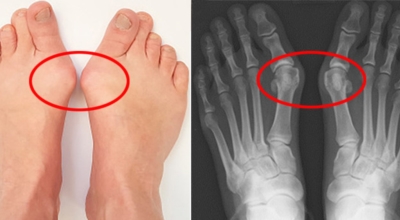

무지외반증은 엄지발가락이 두 번째 발가락 쪽으로 심하게 휘어지며 관절이 안쪽으로 튀어나온 것을 말합니다. 무지외반증은 발가락이 단순히 휘는 정도가 아니라 튀어나와 통증을 일으키는 병입니다. 따라서 발의 볼은 넓어지며, 조금만 조이는 구두를 신어도 통증을 느끼게 됩니다. 또 엄지발가락이 두 번째 발가락을 밀어 둘째 발가락도 함께 변형되어 뒤틀어진 변형을 만들 수 있답니다.

변형이 악화되면 엄지발가락이 두 번째 발가락과 겹치거나 관절이 탈구되어 전반적으로 디디기 어려운 발이 되기도 합니다. 건강보험심사평가원의 무지외반증 환자 통계를 보면, 세대별로는 40대 이상에서 가장 많고 성별로는 무지외반증 여성 환자 비율이 남성보다 월등하게 높았다고 해요.

무지외반증은 발가락의 휘어짐 정도로 1단계 ~ 4단계까지 나눌 수 있어요.

1단계 : 15도 ~ 20도 휘어짐, 외관상 변화가 심하지 않음

2단계 : 20도 ~ 30도 휘어짐, 외관상 변화가 확연히 보임

3단계 : 30도 ~ 50도 휘어짐, 2, 3번째 발가락에 변형이 나타남

4단계 : 50도 이상 휘어짐, 정도가 심한 변형과 극심한 통증이 나타남, 정상적인 보행이 어려움

1, 2단계는 경증으로 통증이 나타나지 않으나, 3단계부터 신발을 신거나 쓸리고 눌릴 때마다 통증이 발생합니다. 4단계는 두번째 발가락이 엄지 발가락 위에 높아져 있다고 하며 뼈의 돌출이 심해진 상태라서 극심한 통증을 동반해서 신발을 신는 것 자체가 불편해지기도 합니다.